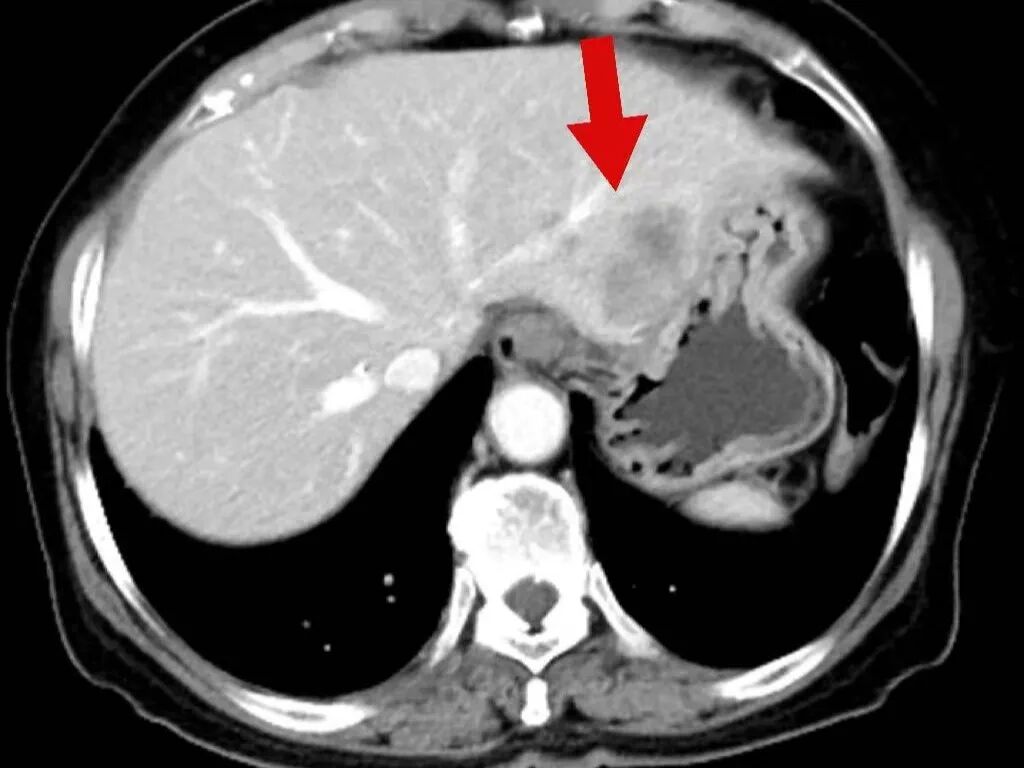

2025年3月17日,肿瘤诊疗中心团队首次为毕女士成功实施BACE治疗。术后患者病情暂时稳定,但5月10日复查显示肺部原发病灶稳定,肝脏转移病灶再次增大。

面对病情反复,团队没有放弃,果断升级治疗方案,决定同期施行BACE联合肝动脉化疗栓塞术,继续强化局部控制。“对于这类晚期患者,局部介入的优势在于能够高效、低毒地控制关键病灶。”介入医学科主任杨亚平说,“BACE联合肝动脉栓塞这类技术既能提高肿瘤部位的药物浓度,又减少了全身副作用,为后续治疗创造了条件。”

令人鼓舞的是,治疗一个月后复查显示,毕女士肺部和肝脏的肿瘤明显缩小,病情得到有效控制,生活质量显著改善。出院时,毕女士激动地说:“本来以为病情已经没希望了,是中山医院的专家们没放弃我,一次次调整方案,现在我不仅不怎么难受了,还能正常生活,真的太感谢他们了!

在玉溪市中山医院肿瘤诊疗中心治疗后,肿瘤在明显缩小